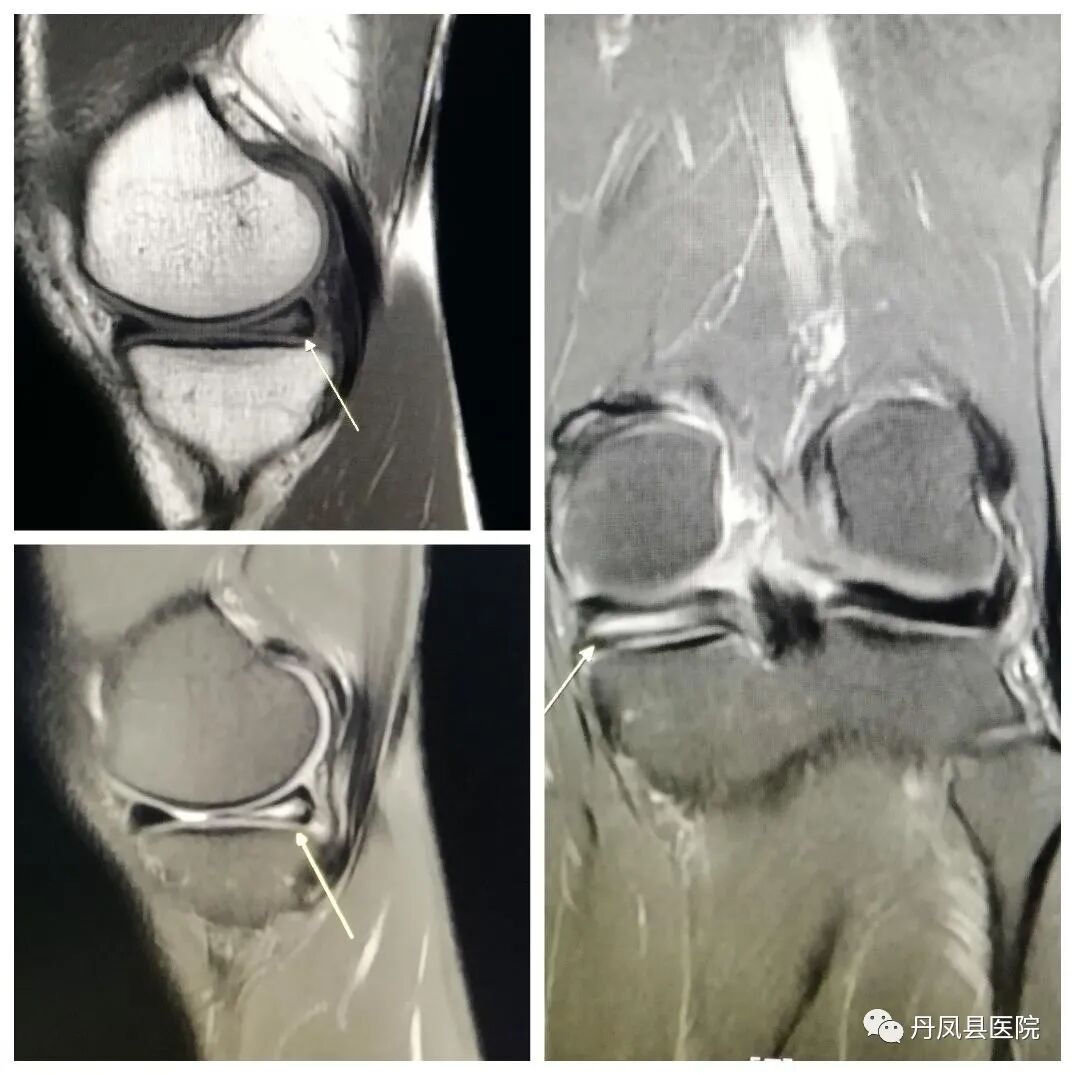

![半月板撕裂.jpg]()

半月板撕裂

优秀的关节成像,清晰显示细微解剖结构、骨骼、关节软骨、韧带等结构。